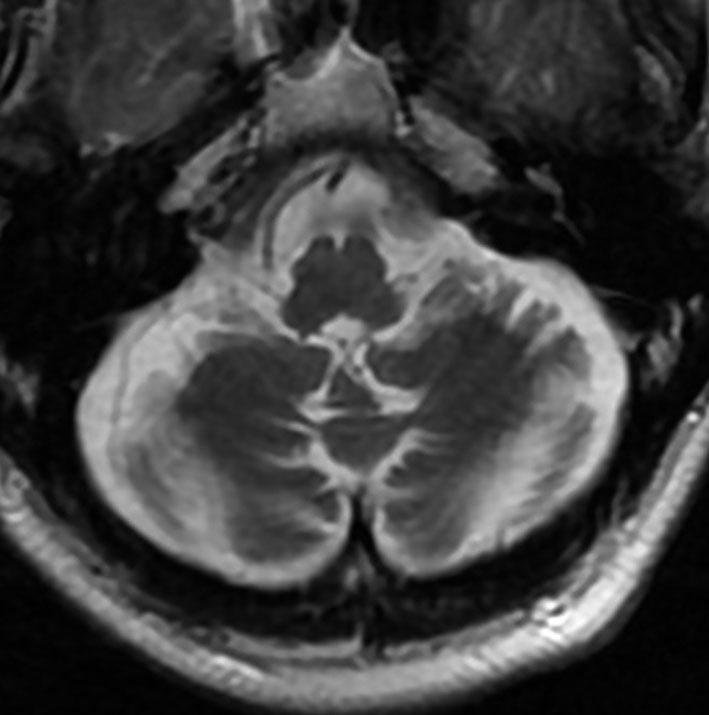

アレビアチン(フェニトイン)やデパケン(バルプロ酸)を何年も服用していると小脳に萎縮がくることがあります。小脳失調症というふらつきがでることは少ないのですが,MRIで小脳が小さくなったようにみえます。

20年以上バルプロ酸の服用をしている患者さんです。左と中央のMRIでは小脳萎縮がありますが,右側の大脳では萎縮は全くありません。小脳症状はありません。